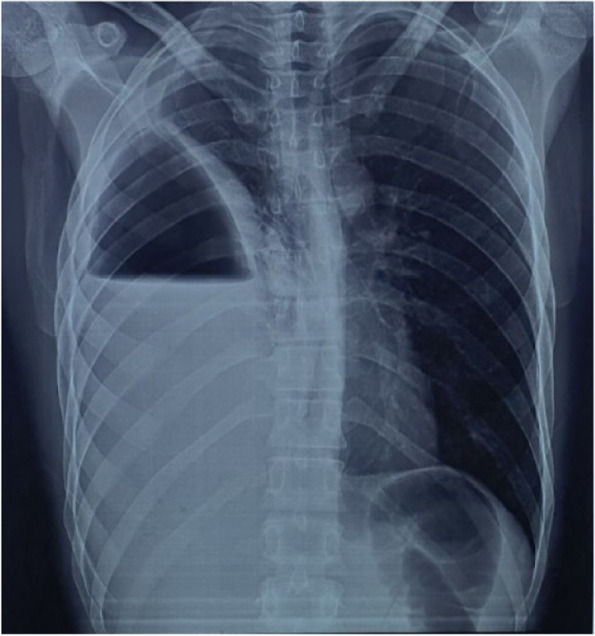

A chest X-ray was performed, which showed a hydro-pneumothorax on the right side, while the left hemithorax appeared normal (Fig. 1).

Fig. 1.

Chest x ray at admission showing a right hydro-pneumothorax